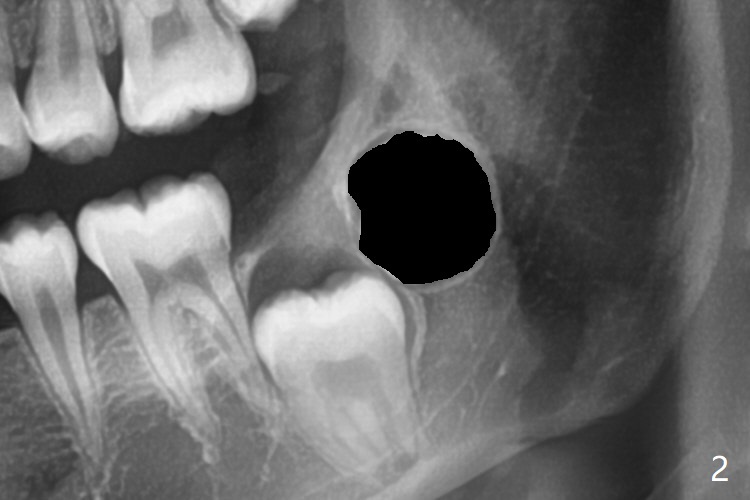

Treatment planning of surgical access to the impacted 7 (Fig.1) before CT analysis (to be canceled due to finance) include extraction of 8 (Fig.2) and removal of the bone coronal to 8 (Fig.3 red) so that there will be no bony block to 7 eruption (Fig.4). Place PRF or collagen plug in 8 socket to facilitate healing (Fig.3). Attach a retraction chain to the occlusal or buccal surface of 7 (Fig.6 pink) whenever it is convenient in term of hemorrhage and access (as mesial as possible). Remove 16 niti wires for brushing when the patient arrives. Cut 18 ss wire longer in the LL end (Fig.6 green to be bent to hook power chain (yellow)). Incision is shown as red in Fig.5. After 3 month delay, the thick buccal plate is removed from LL8 (1st) and 7 (2nd in sequence, as compared to Fig.2) to expose these unerupted teeth. In fact CT is not taken to decrease budget on the divorcing parents. A retraction chain is placed before extraction of LL8 with an intention to reduce hemorrhage (Fig.7). Although extraction requires several sectioning of the tooth, hemorrhage is mild to moderate. Instead of PRF and sticky bone (as compared to Fig.3), Osteogen plug is placed in the socket (Fig.8 OP). The bony septum between the 2 sockets is intentionally kept in place (*). 事实的确这样发生(图九:*)。埋伏牙不仅上移(^),而且远中移动(>),因为牵引方向(红虚线(橡皮筋),挂在上牙弓丝(图九:20ss:图十:18ss(之前))远端勾,积极牵引三个星期)。下次左上7放置舌侧纽扣,让病人更换橡皮筋。其实纽扣粘不住,上牙弓丝远中勾也不现实,只能使用橡皮筋挂在左上6,经常断。术后6个月,左下7继续上移(图十一)。这种低效率牵引仍然有效,牙齿继续上移,牙根长长(图十二:空箭头),但是受到左下6远中阻挡(*),所以下次在左上7咬合面装置舌侧纽扣和closed spring,改善牵拉方向(红箭头)。